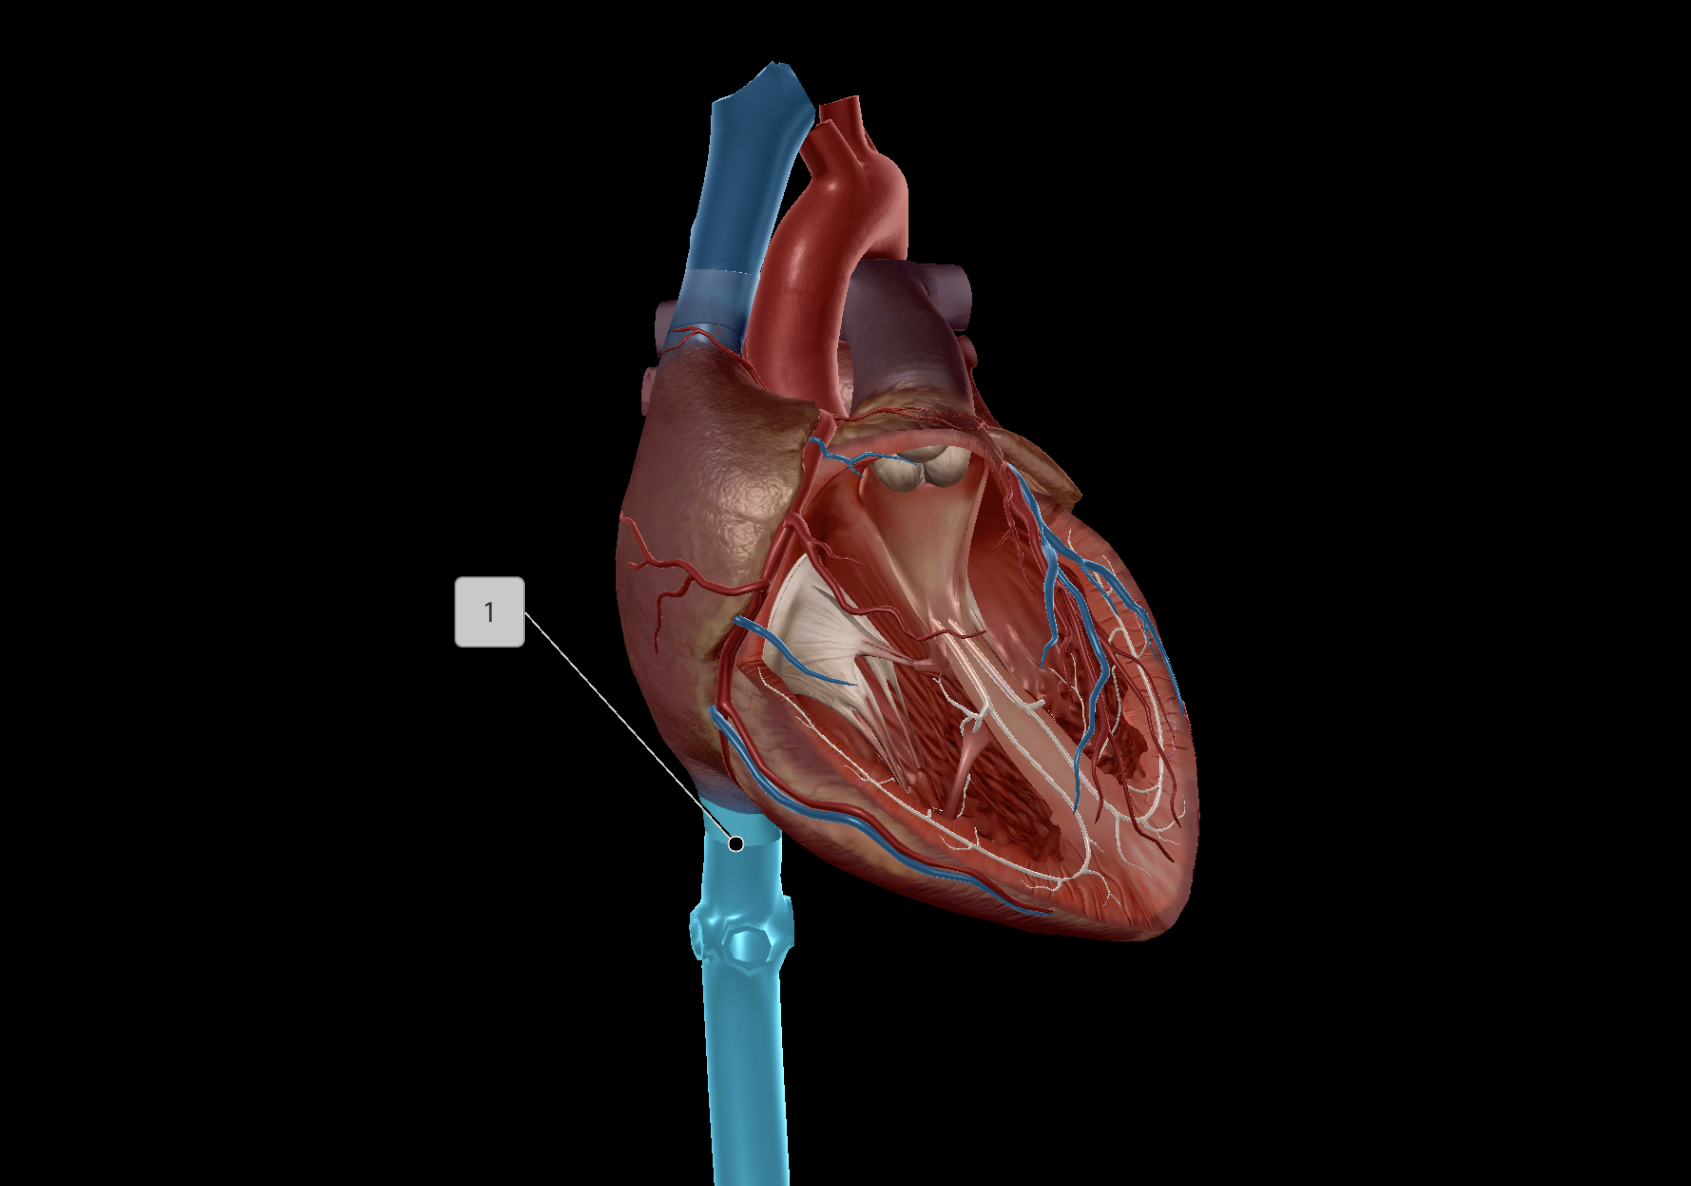

Inferior Vena Cava

Superior Vena Cava

Pulmonary Trunk

Pulmonary Artery

Left Atrium

Left Ventricle

Right Ventricle

Right Atrium

Papillary Muscle

Chordae Tendineae

Tricuspid Valve

Bicuspid Valve

Aortic Valve

Pulmonary Valve

Interventricular Septum